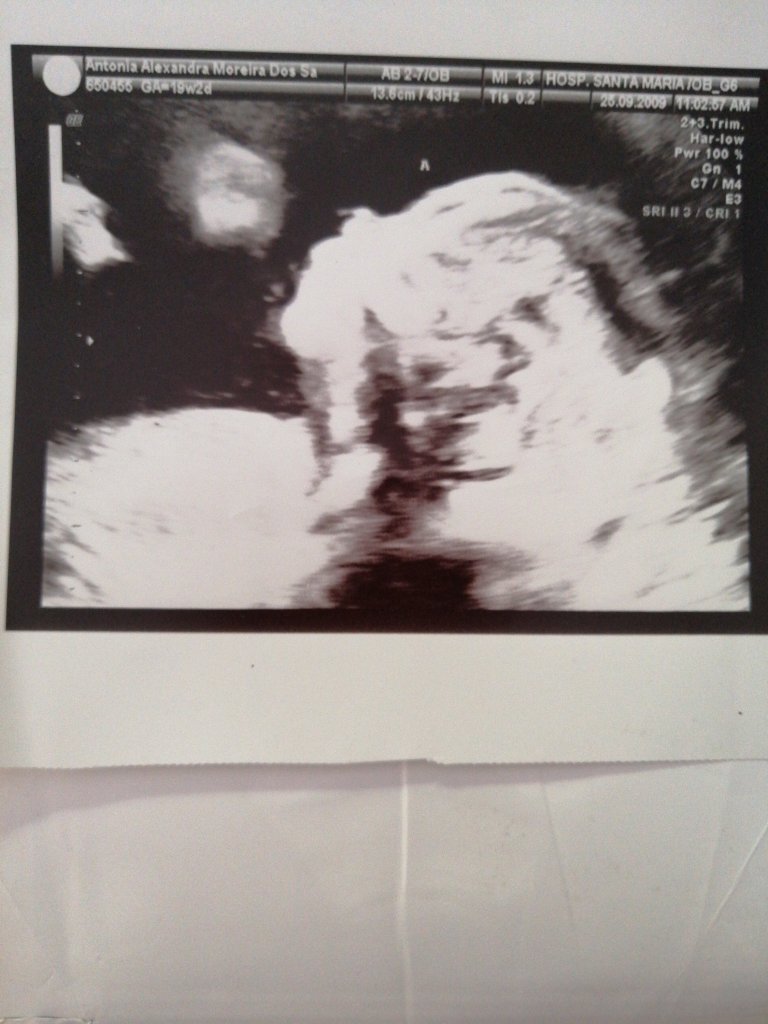

Mesmo assim a médica explicou todos os riscos acrescidos da minha gravidez, o facto de ter 2 placenta de 1 delas ter 2 bebés, de ser o único exame possível, pois as análises bioquímicas, no caso das gravidezes de múltiplos, não são fiáveis, da situação do bebé n1…